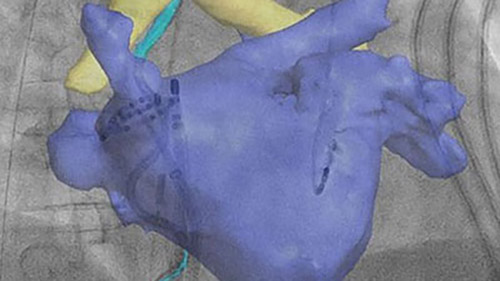

Provides a 3D image of the heart based on either a pre-interventional CT or rotational angiography image taken during the procedure. EP navigator gives you fully automatic segmentation and registration of LA-PV anatomy for intuitive 3D catheter guidance. Registration can be exported to all standard mapping systems to manage X-ray dose, save time, and re-registration.

Provides 3D visualization of the anatomy to plan the optimal therapeutic approach. Intra-procedural high-resolution rotational angio is an alternative to pre-procedural CT or MR. And the 3D-RA scan exports to St. Jude Ensite and Biosense CartoAlara.